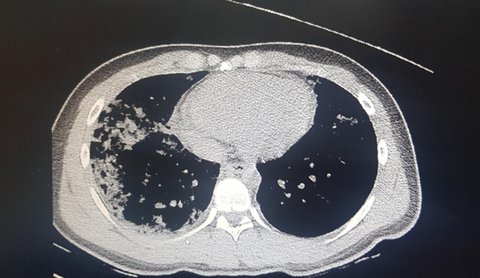

숨진 정모군 부모가 24일 공개한 컴퓨터 단층촬영(CT) 사진을 보면 기관지 아래인 폐 뒤쪽과 가장자리에 병변이 발생한 것을 확인할 수 있다.

CT 사진은 지난 13일 오후 9시 8분 영남대병원에서 찍은 것으로 당시 정군 체온은 40도를 넘었다.

폐 사진을 본 대구·경북 지역 전문의들은 정군 예후가 단기간 급격히 나빠진 것으로 해석했다.

몇몇 전문의들은 '코로나19 전형'으로 해석하는 간유리음영(Ground-grass opacity, GGO)이 보인다고 했다.

경북지역 이비인후과 전문의 B씨는 "단순히 CT만으로는 폐포에서 바이러스성 폐렴이 일어난 것으로 보이는 양상이다"며 "진료기록에 초반 며칠간은 열이 40도 이상인데도 백혈구(WBC) 수치가 정상인 걸 보면 세균성이 아닌 바이러스성 폐렴으로 추정할 수 있다"고 밝혔다.